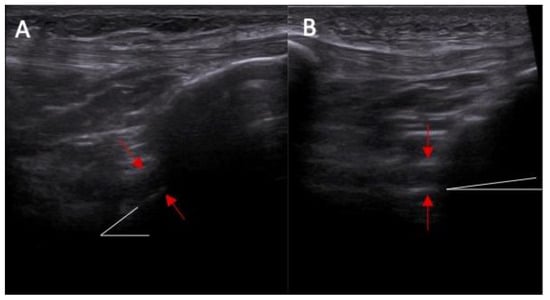

Figure 5.

The proximal attached (marked with arrows) view of the ACL tear with edema. (A) arthroscopy view; (B) MRI view; and (C) ultrasound view—swelling of the ACL proximal attached to lateral femoral condyle.

Swelling of the ACL/PCL on ultrasound was more common in patients with an ACL injury than in those without an ACL injury (88% vs. 0%, respectively, and p < 0.0001) (Figure 6 and Figure 7). OR = incalculable.

Figure 6.

(A) Ultrasound view of swelling/scarifications of the ACL/PCL compartment with change of the morphology of the posterior joint capsule complex marked with the arrows and (B) normal view. PR—right.